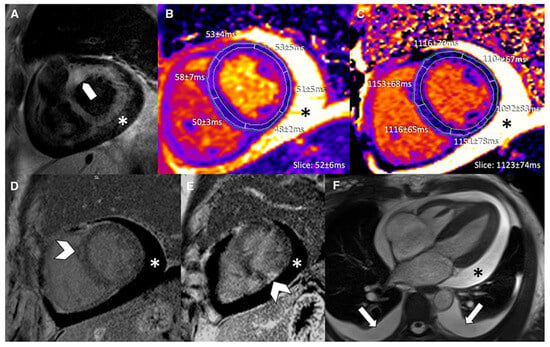

Figure 6.

A 65-year-old female with reduced EF (24%), LV dilation (EDV/BSA: 153 ml/mq), and no significant coronary artery disease. No hyperemia (a, EGE ratio < 4), neither edema (b, T2 ratio < 2) nor LGE (c), was found: oLLC were negative for suspected acute myocarditis. Native T1 was severely increased (d), with a mid-ventricular mean value of 1190 ms; ECV (e) mean value was 35%, and T2 mapping was slightly increased (f, mean value: 52 ms). Both T1 and T2 criteria were positive according to nLLC, and the diagnosis of viral myocarditis was confirmed by EMB. EF—ejection fraction, EDV—end-diastolic volume, BSA—body surface area, EGE—early gadolinium enhancement, STIR—short tau inversion recovery, LGE—late gadolinium enhancement, oLLC—old Lake Louise Criteria, ECV—extracellular volume, nLLC—new Lake Louise Criteria, and EMB—endomyocardial biopsy. Reproduced from: Cundari, G., et al. (2021) [17]. Licensed under CC BY 4.0 (https://creativecommons.org/licenses/by/4.0/ accessed on 15 December 2025).